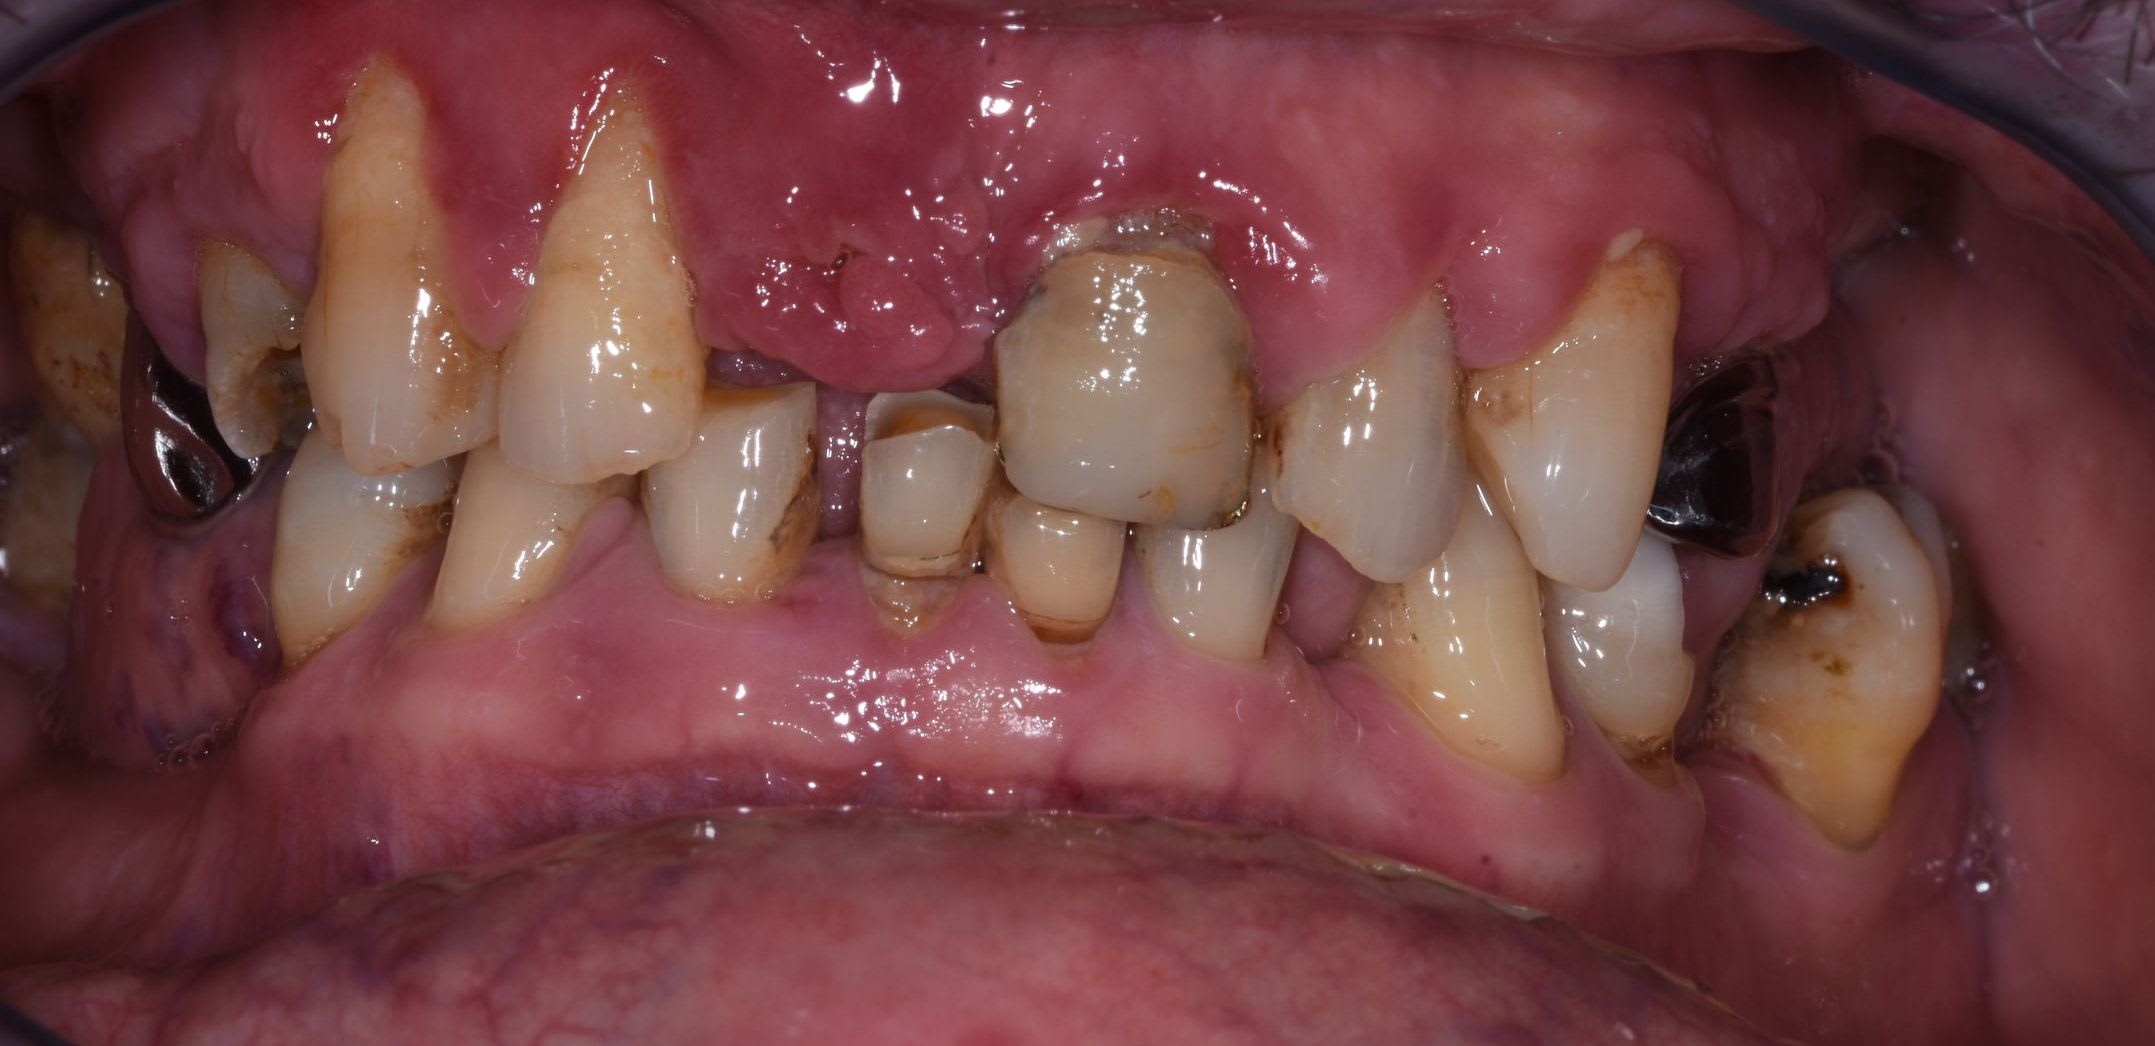

J'ai un patient de 60 ans, bonne santé générale. Rémission de maladie auto-immune lourde mais stable depuis 3 ans. Non fumeur.

La première consultation, il y avait de la plaque partout.

Une motivation au brossage, un det et un surfaçage + tard, histoire de remettre les choses en état, je me retrouve avec ce type de gencive : voir les photos.

Depuis les photos, j'ai viré la couronne de 21 et refait la provisoire, ça va mieux, mais pas tip top pour la gencive.

J'ai passé une fraise à fine granulométrie (bague blanche) pour laisser la racine encore + lisse qu'avec les curettes.

Des papilles hyperplasiques au delà de leur position physiologique et un rapport dentaire-os 1/2. Tu dois taper dedans à la turbine pour ramener l’ensemble à plat. Raccourcir tes chicots. Mais avant calage postérieur ++++, sans ça, ne rien toucher. Là, c’est de la dentisterie de guerre.

Au sondage on passe les 3 mm quasi partout sur les incisives maxillaires. Ailleurs, de façon générale, ça s'est bien refermé. Pas partout cependant, il doit rester une poche sous une molaire qui s'est versée (de mémoire, j'ai pas son dossier avec moi, juste pris la radio et les photos pour les poster)

Tu as des migrations secondaires et une dv effondrée, tu ne peux que coiffer au moins toutes les maxillaires entre autre pour rétablir un angle I/i correct, et des courbes compatibles.